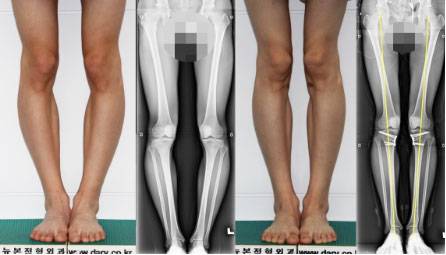

| 외반슬(엑스다리)인데 무릎이 벌어진 환자

이 환자는 무릎 사이가 벌어져 있었다. 물론 11자 다리를 만들고 싶은 마음에 나를 찾아왔고 수술을 진행했다. 오른쪽 사진은 수술 후 사진과 x-ray 사진이다. 무릎은 과거보다는 간격이 줄었지만 붙지 않고 벌어져 있다. 일반적으로 말하는 오다리인 것이다. 엑스레이 사진을 보면 다리의 정렬은 약간 안쪽으로 들어가 있는 것을 확인할 수 있다. X-ray 상에서는 엑스다리이다.

정렬을 맞출 때 0˚가 기준이지만 예쁜 다리의 기준은 ±∠2˚ 또는 여유 있게 보는 의사들은 ±∠3~4˚ 까지도 허용한다. 내가 수술하는 기준은 ±∠2˚ 이내이다. 즉 위의 사진의 환자는 기준에 맞춰 약간 안쪽으로 각도를 두었음에도 무릎은 붙지 않았던 환자이다. 만약 여기서 각을 더 틀었더라면 환자 무릎이 붙었을 것이고, 만족스럽게 생활을 하다가 나이가 들어 외측 관절염이 발생해 재수술을 하거나 인공관절을 할 수밖에 없는 상황이 되었을 것이다.